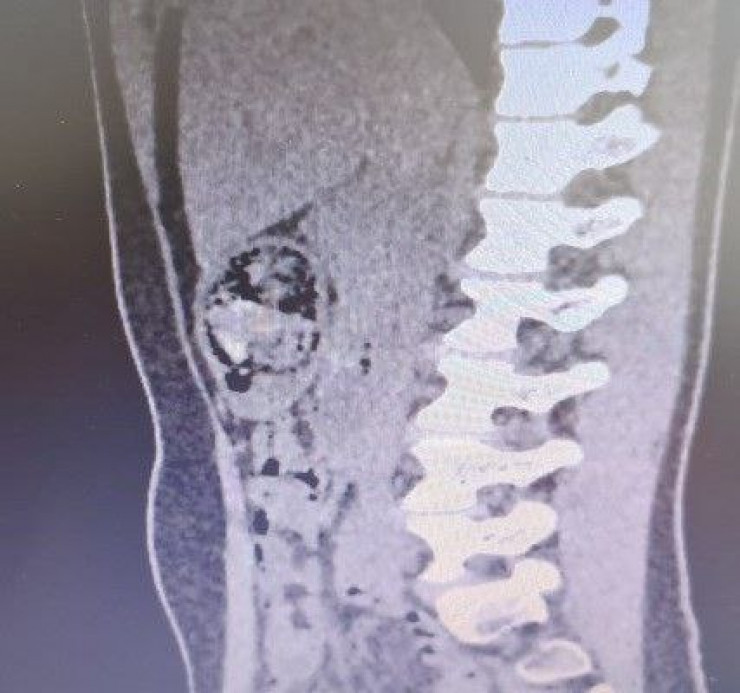

В хирургическом отделении Жамбылской областной многопрофильной детской больницы 12-летней жительнице Тараза провели операцию: из ее желудка извлекли килограммовый волосяной ком, передает Tengrinews.kz со ссылкой на пресс-службу Министерства здравоохранения.

В ходе оперативного вмешательства из желудка пациентки было изъято около 1,2 килограмма инородного тела – трихобезоара (волосяной ком). Операцию провела бригада специалистов: заведующий хирургическим отделением Эльбрус Салпагаров, заведующий операционным отделением Канат Дуйсебаев и анестезиолог Бахтияр Баялиев. Сейчас девочка идет на поправку.